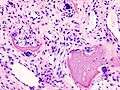

Damaged cartilage from sows. (a) cartilage erosion (b)cartilage ulceration (c)cartilage repair (d)osteophyte (bone spur) formation.

Histopathology of osteoarthrosis of a knee joint in an elderly female.